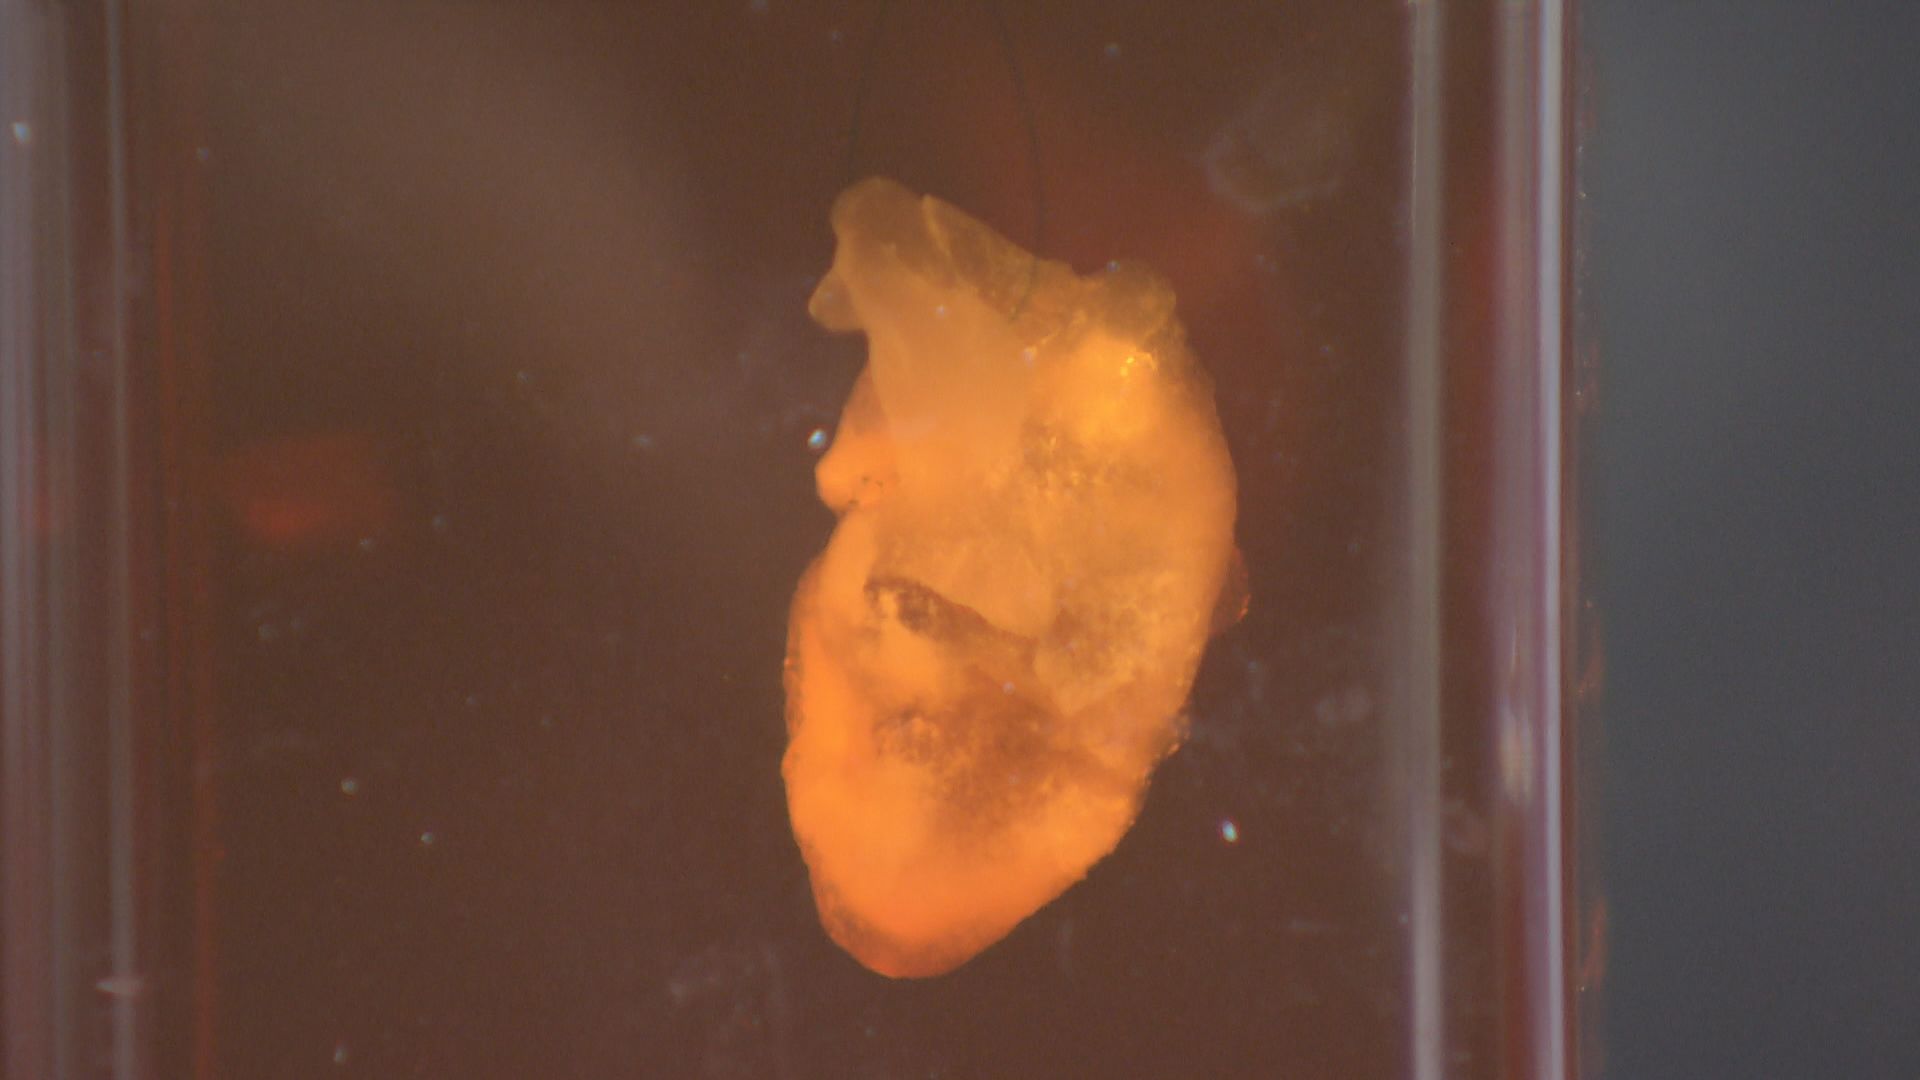

■「ぶら下げた方がいいんです」強く拍動した心臓

万博・開幕のおよそ1年前、長谷川さんと奥田さんの2人は、心臓の形をしたコラーゲンをスポンジ状に加工し、心筋細胞を染み込ませ、人の体温と同じ37℃前後で、外的な刺激を与えなくても自律拍動させるところまで開発を進めていた。

しかし、その心臓を横に寝かせると、目視で拍動がわかるレベルには達しておらず、展示するには程遠い状態だったという。

そこで奥田さんが提案したのが、実際の心臓と同じく、縦にして吊り下げるという手法だった。

iPS心臓モデルにナイロンの細いワイヤ―を通し、培養液の中で吊り下げると、実際の心臓と同じように拍動したのだ。

【クオリプス・長谷川光一博士】「寝かしたままで、鏡を置いて立っているように見せることができればいいという意見もあったんですけど、奥田さんの『いやいや吊ってみましょうよ』っていうアイデアで吊り下げてみたら、平面でいるときよりも、心なしか拍動が自然の形に近いのか、強い感じがしてですね、不思議だなと思って」

「万博が終わったら、何が起こっているのか研究しようと思っているんです。吊り下げると拍動が強くなるので、何かしらのことが起こっていると思うんです」

奥田さんの「心臓を吊り下げる」という発想には、研究を見守っていた澤教授も驚いたという。

【大阪大学・澤芳樹特任教授】「もう突然、開幕の1年ぐらい前に、奥田君が僕に『心臓が動き出しました』って言ってくれたんです。それまでは、ほとんど動いてなかったんですよ。こんなこと技術的にできるわけがないと思っていたら、奥田君が『できた』っていうから、『ほんまか?』って言って。それで、奥田君が『ぶら下げた方がいいです』と」

「糸で吊ることで、動き出すということがわかったので、これも『サイエンス』ですよね。吊らなかったら動かないのに、吊ったら必ず動くんだというところで再現性がある」

「なぜ吊ったら動くかということが大事で、おそらく心筋細胞に与える重力とか、いろんな影響があるのかもしれない。もともと持っている遺伝子じゃなくて、環境因子がそういう影響を与えて、細胞の性格を変えたがために、寝ていたら動かなかったのが、立てたら動くようになるというね」

■「1個1個が生き物。同じ子はいない」

【クオリプス・奥田雄一 博士】「一番理想的には強く、長くもってくれるのが一番いいんですけど、やっぱり、いいとこどりにはならないので、めっちゃ元気な子は短命やったりするし、すごく緩やかに息長く拍動したりする子もいるんで」

「どれが一番いいかというのは、その時々の見た目で判断するしかないんですけど、結構個性分かれますね。1個1個がやっぱり生き物なんで、同じ子はいないんですよね」